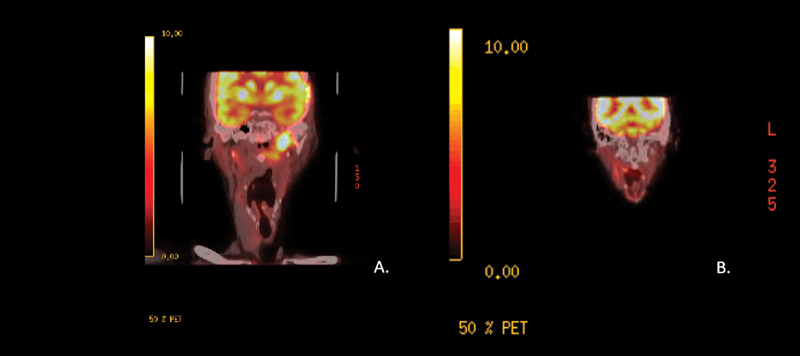

Nasopharyngeal Carcinoma: Case Presentation and Literature Review of Treatment Innovation with Immunotherapy.

Nasopharyngeal carcinoma (NPC), a rare head and neck malignancy, arises from the epithelial lining of nasopharyngeal mucosa. The confluence of various risk factors, such as latent Epstein-Barr virus infection, genetic susceptibility, smoking, alcohol consumption, and high nitrosamine diet, is thought to contribute to NPC pathogenesis. Radiation therapy serves as the mainstay of treatment for early stage while concurrent chemotherapy and radiation are the basis of treatment for locoregional advanced disease with overall 80% five-year survival rate. Recurrent or metastatic disease pose treatment challenges as reirradiation, repeat cycles of chemotherapy, and surgery follow with high likelihood of treatment toxicity or postoperative morbidities. Typically reserved for nonresectable recurrent or metastatic disease, immunotherapy serves as novel treatment for NPC. NPC tumor microenvironment predominated by a dense infiltrate of immune cells hosts an ideal target for immunotherapy. Several clinical trials have investigated the efficacy of anti-programmed cell death protein 1 antibodies such as pembrolizumab, nivolumab, and camrelizumab with promising results. Treatment of recurrent and metastatic NPC remains a challenge; however, the advent of immunotherapy has provided additional options and potential for preventative and therapeutic measures.